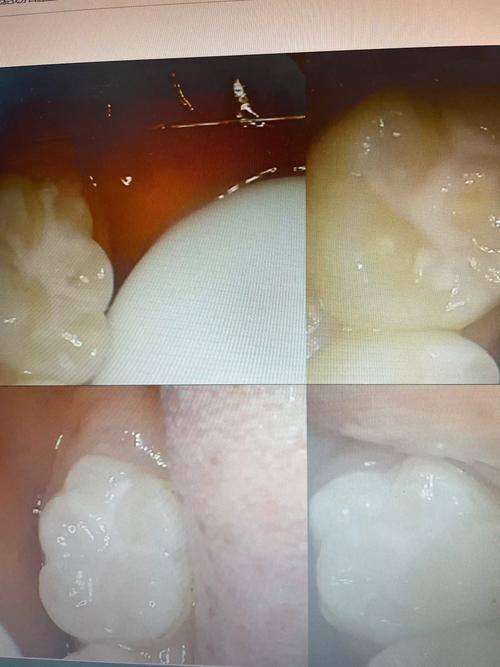

牙齿修复:可开展烤瓷牙、全瓷牙等多种牙齿修复项目,结合精良设备与个性化方案,有效修复牙齿的形态与功能。

山东泰安新泰巩键口腔树脂补牙:198元起/颗

山东泰安新泰巩键口腔烤瓷牙:880元起/颗

山东泰安新泰巩键口腔全瓷牙:1680元起/颗